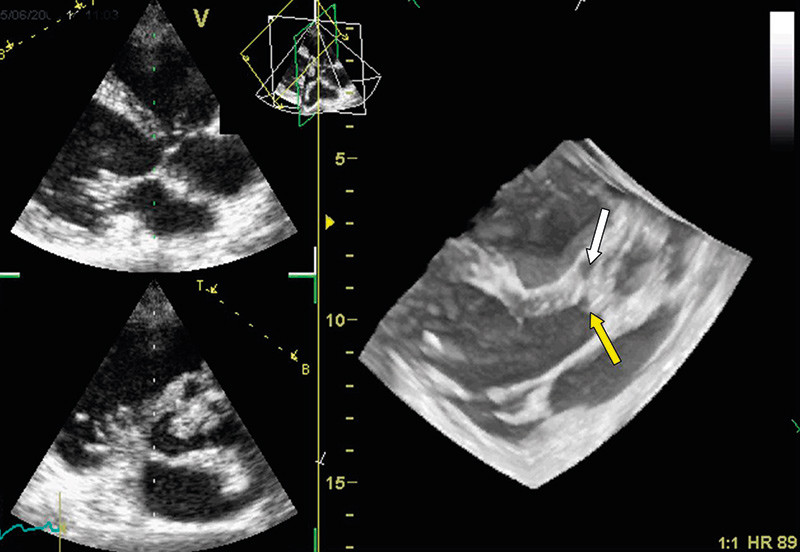

The evaluation of heart valve disease using 3D echocardiography has been validated in different studies. To date, the best documented have been diagnostic studies of pathological mitral valves (9) – (12). During the last decade, there has been a change in the surgical treatment of mitral valve disease. New surgical techniques have enabled the repair of mitral defects in many patients who would previously have had to have valve replacement. Reparative surgery of this kind requires a very high degree of precision in diagnostics of the mitral valve’s form and function, to enable the correct surgical method to be employed. In our own department, we use 3D echocardiography to investigate patients with mitral valve regurgitation, to enable us to locate exactly the damage to the valve (Figure 2). We have benefited especially from the so-called «surgeon’s view» from the left atrium, where the entire mitral valve can be represented in the same image as shown in Figure 2.

Figure 2  Transthoracic recording of the mitral valve viewed from the left atrium («surgeon’s view»). The white arrowhead…

Figure 2 Transthoracic recording of the mitral valve viewed from the left atrium («surgeon’s view»). The white arrowhead marks prolapse of the posterior mitral valve seal, which comprises the medial and posteromedial thirds (P2 and P3, respectively).

Fig 3  Transthoracic recording in patient with aortic valve endocarditis. The yellow arrowhead marks valvular vegetations…

Fig 3 Transthoracic recording in patient with aortic valve endocarditis. The yellow arrowhead marks valvular vegetations and the white arrowhead the abscess cavity in the aortic root anteriorly.